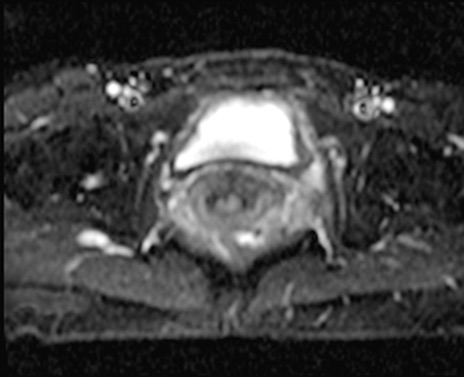

MRI(4日後)